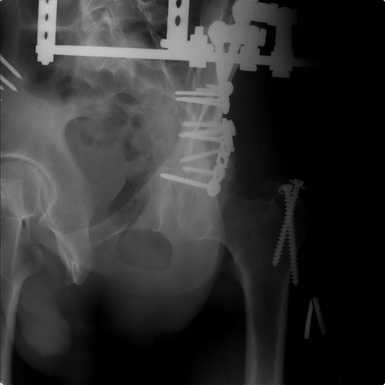

Добрый вечер уважаемые коллеги. Прошу прощение за долгое молчание( компьютер был в

долгосрочном ремонте). Больного с 9-ти месячной травмой таза мы прооперировали.

Оценив свои возможности и совместив с вашими рекомендациями и советами( большое спасибо

Рункову!), пошли задне-наружным доступом, с отсечением большого вертела. Закрепились

2-мя пластинками. Сверху закрепили аппаратом( передней рамой). На область перелома самого

гребня повздошной кости не вмешивались. Снимки высылаю. Жду ваших отзывов и комментариев.

Всем большое спасибо за активное участие в лечении больного. С ув.Андрей